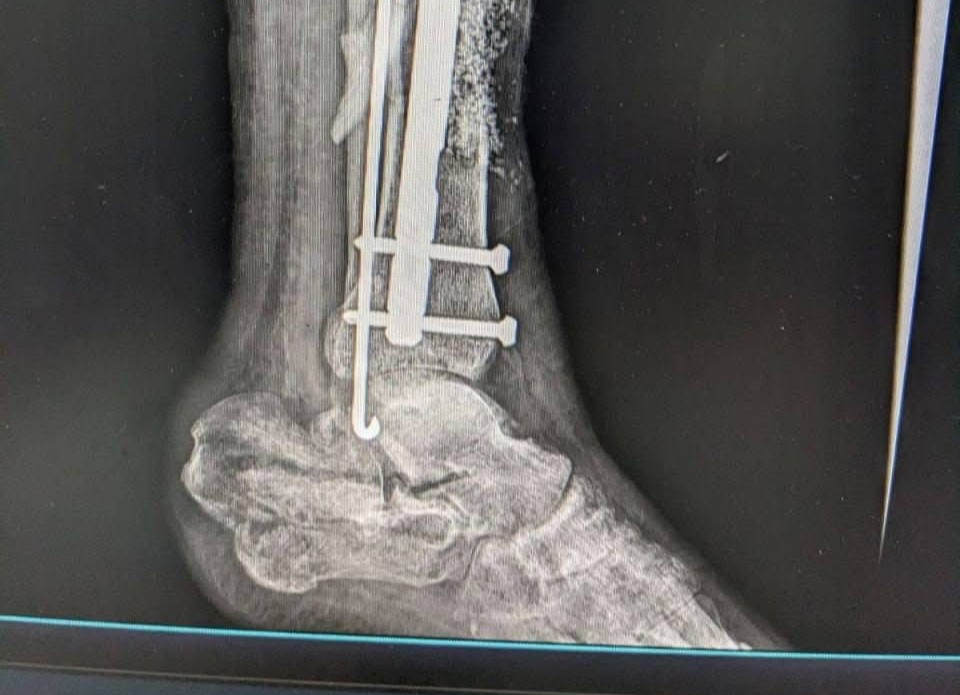

«Навіть під час повномасштабної війни українські медики не зупиняються: вони виконують складні реконструктивні операції, рятують життя та дарують нашим захисникам шанс знову жити повноцінно», — йдеться в дописі.